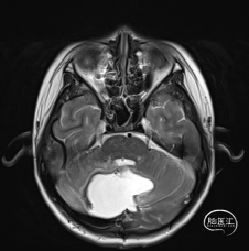

术后MRI

枕下后正中开颅小脑肿瘤切除术

术后病理